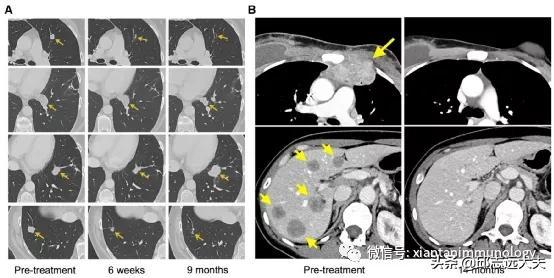

一名错配修复熟练的转移性结肠癌患者接受了自体TIL产品的治疗,该产品包含约75%的CD8+细胞,识别来自KRAS基因热点(G12D)突变的新生抗原。这导致了所有转移性肺病变开始消退。其中一个在9个月后进展,随后被切除,使患者无疾病生存。

靶向mSNV来源的新生抗原T细胞,可以介导持久的肿瘤消退,而不会对正常组织造成任何毒性。然而,需要注意的是,大多数接受治疗的患者(尤其胃肠道癌症患者),仍然对这种治疗没有反应。